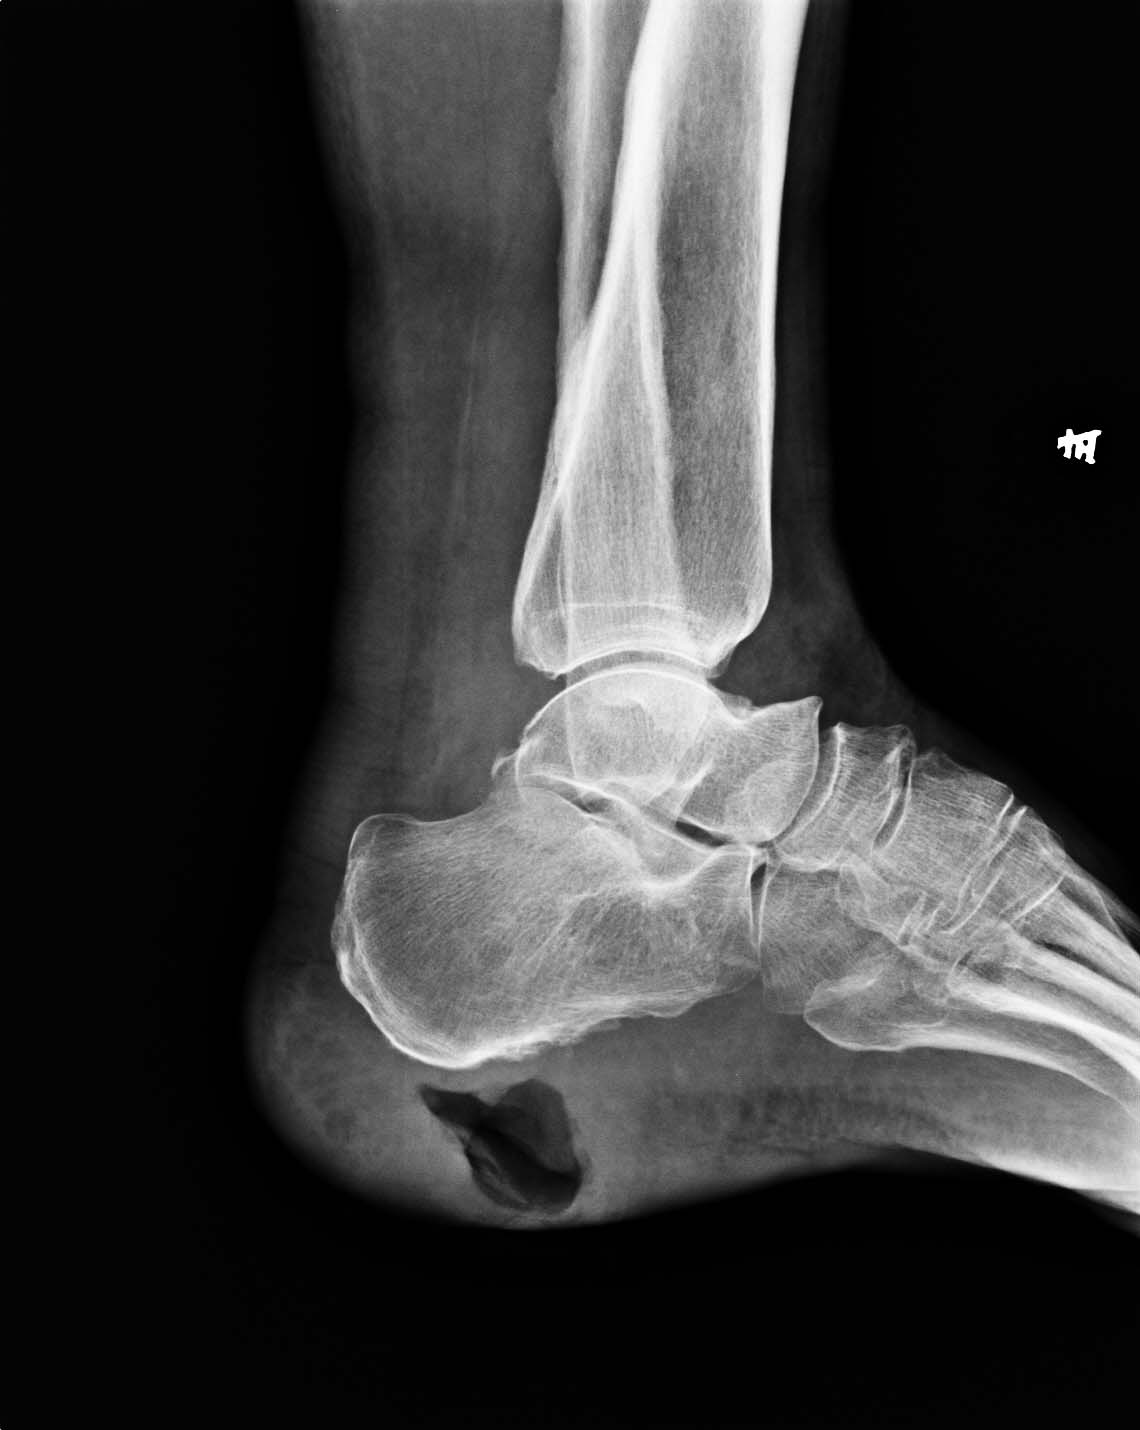

女,65岁,跟部软组织溃疡已二年,现跟骨下方见骨膜反应,x线报告上如何诊断。

跟部软组织感染、窦道形成并跟骨骨膜炎

1、左跟部局限性软组织缺失

2、左跟骨骨膜炎,建议密切观察,除外跟骨骨髓炎

腓骨骨膜增厚,不规则。建议加摄。

足跟部软组织感染、窦道形成并跟骨骨膜炎。